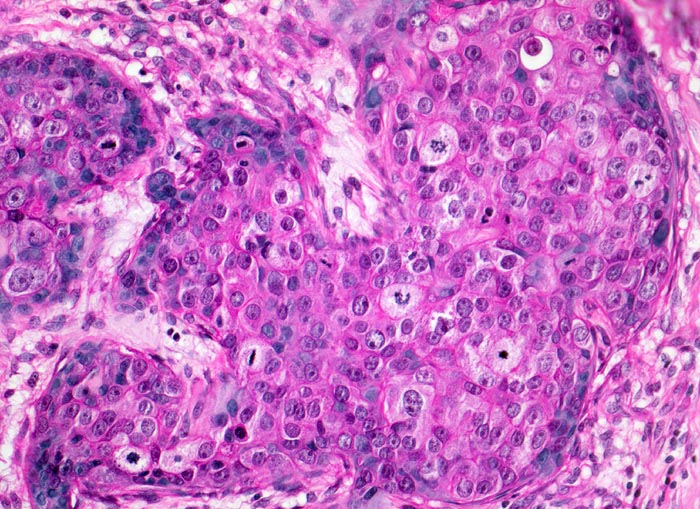

wenig differenziertes invasives duktales Mammakarzinom

Solide Tumorzellplatten mit zahlreichen Mitosen.

Makroskopisch: derber weisser Herd von 2.2cm Durchmesser im oberen äusseren Quadranten.

Die Patientin hatte bei der Selbstuntersuchung einen harten Knoten in der rechten Mamma palpiert. Nach dem Nachweis von Karzinomzellen in der Feinnadelpunktion wurde eine Lumpektomie durchgeführt. Die intraoperative Schnellschnittuntersuchung ergab tumorfreie Resektionsränder.

Histologie

200